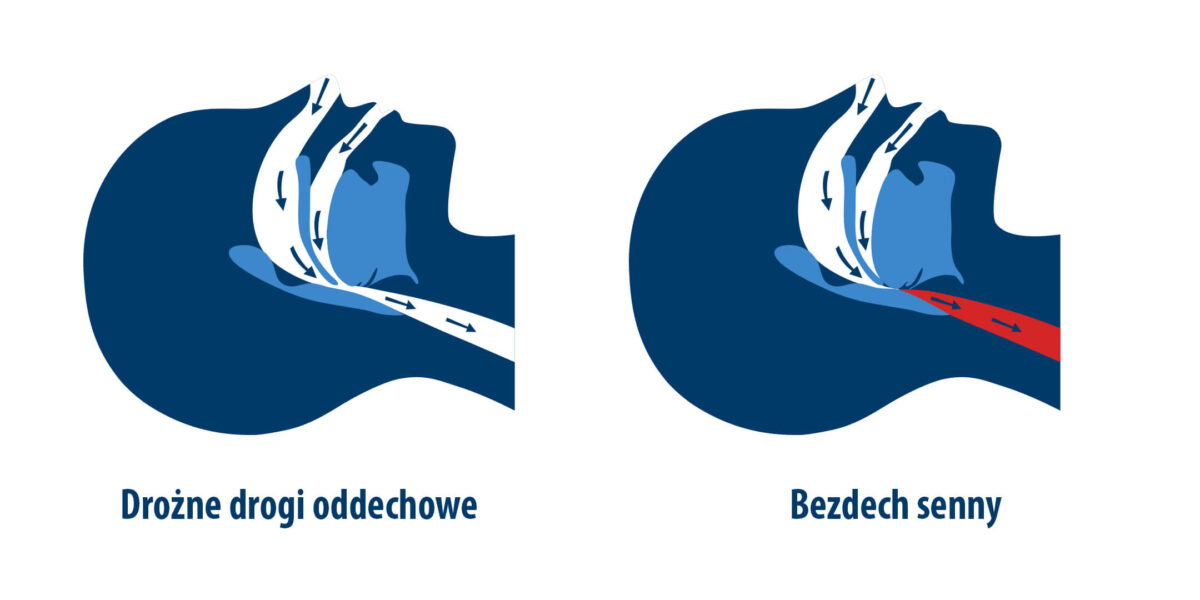

Pacjenci z bezdechem sennym

Pulsoksymetr jest szczególnie przydatny w opiece nad osobami z bezdechem sennym (sleep apnea), chorobą charakteryzującą się epizodami przerwania oddychania w czasie snu, które prowadzą do spadków saturacji i niedotlenienia organizmu w nocy co może prowadzić do przewlekłego zmęczenia, zaburzeń koncentracji, a w dłuższej perspektywie do rozwoju nadciśnienia tętniczego i chorób sercowo-naczyniowych (16). Monitorowanie nocnych zmian wysycenia krwi tlenem pozwala ocenić, jak często i jak głęboko występują te spadki, co stanowi ważną informację przy ocenie skuteczności stosowanego leczenia. Dzięki danym uzyskanym z pulsoksymetru lekarz może podejmować decyzje terapeutyczne, np. modyfikować ustawienia aparatu CPAP lub wprowadzać inne interwencje mające na celu poprawę jakości snu i zapobieganie przewlekłemu niedotlenieniu (17).